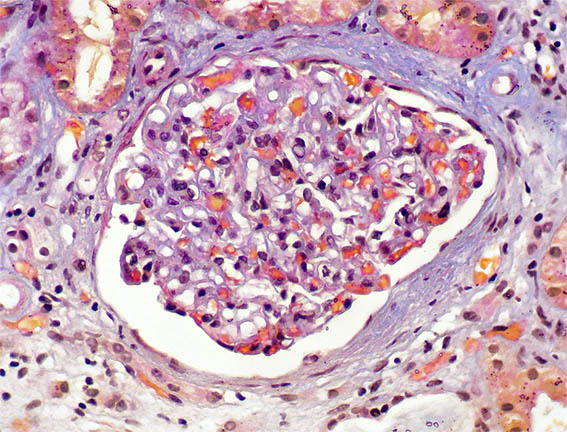

Figure 1. Masson´s trichrome stain, X400. Normal glomeruli; there is periglomerular fibrosis.